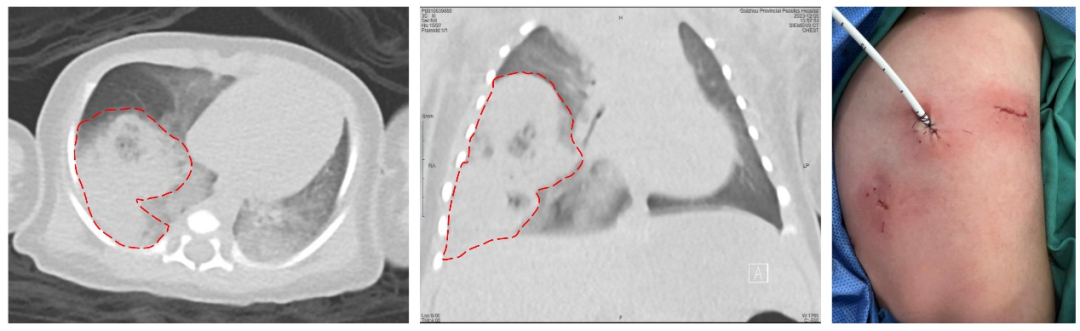

图一、图二 红色虚线指示右肺下叶病变;图三为患儿微创手术切口

在上海儿童医学中心贵州医院儿童普胸外科、新生儿科、麻醉科、手术室团队的密切配合下,由李飞副主任医师为患儿顺利完成了胸腔镜下右肺下叶基底段切除术,小辛术后病情稳定。

据李飞副主任医师介绍,新生儿病情变化快,对手术打击承受能力弱,进行胸科手术风险巨大,实施手术面临很大的挑战。查阅文献及相关报道,小辛的手术为我省第一例新生儿胸腔镜肺段切除手术。为小辛成功实施手术既体现了上海儿童医学中心贵州医院多学科过硬的技术本领,也彰显了上海儿童医学中心贵州医院作为儿童区域医疗中心的责任与担当!